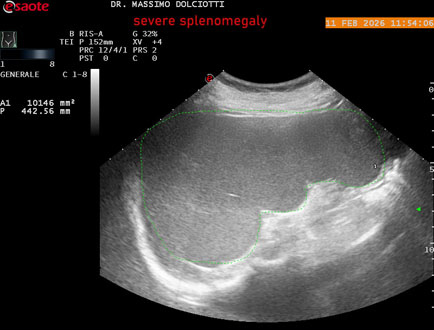

Data inserimento: 18/02/2026

Ecografia del: 11/02/2026

Strumento: Esaote MyLab Eight

Sonda: Conevx Multifrequenza 1-8 MHz

Età Paziente: F 68 anni

Motivazione dell'esame: follow up di splenomegalia.

Commento all'esame: le immagini ed il video documentano la milza con ecostruttura normale e morfovolumetria superiore alla norma, con diametro bipolare di 159 mm (v.n. 70-120 mm) ed area di sezione di 101 centimetri quadri (v.n. < 47 centimetri quadri).

Conclusioni: splenomegalia di severa entità (severe splenomegaly).